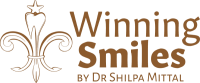

Apicoectomy

What is it?

Apicoectomy is a surgical procedure in which a flap is reflected and the infection associated with a certain tooth is removed along the root tip. A bone substitute is placed. The flap is closed and stitched.

Who needs it?

- When a previous root canal treatment has gotten reinfected.

- When all atraumatic methods of removing the infection have been exhausted.

- When a cyst is formed due to a long-standing abscess.